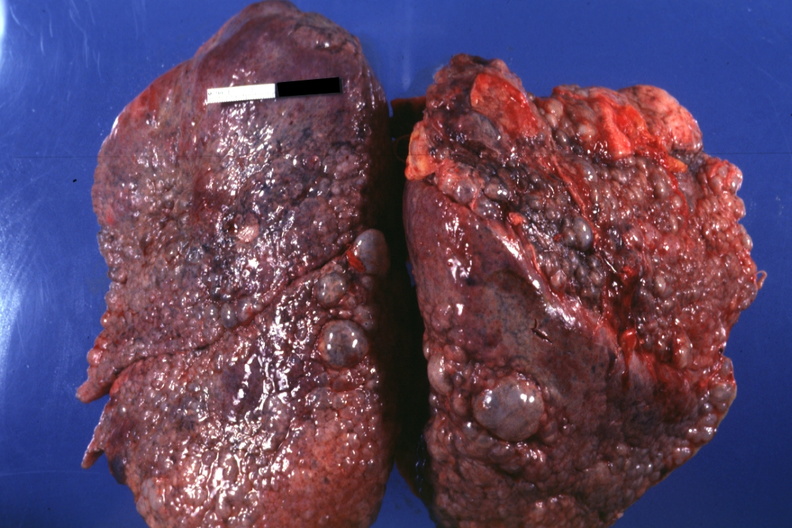

肺纖維化圖片

_雙肺肺纖維化肺灶